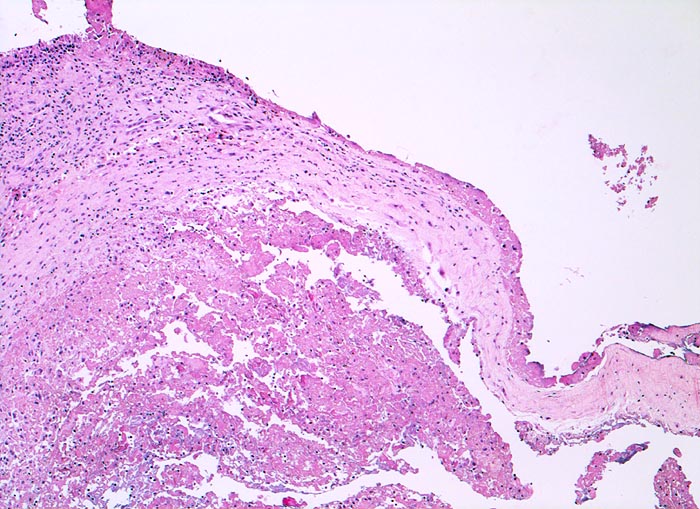

PathoPic ID 4774 - fibrinöse Synovialitis bei chronischer Polyarthritis

fibrinöse Synovialitis bei chronischer Polyarthritis

Systemerkrankung/Immunpathologie

Synovialis

Knochen, Knorpel, Gelenke

Anstelle der synovialen Deckzellschicht sind die Zotten der Synovialis von einer dicken

Fibrinschicht durchmischt mit Granulozyten bedeckt.

Bekannte seropositive chronische Polyarthritis.

Eine akute fibrinöse Entzündung findet sich häufig bei einer floriden chronischen Polyarthritis.

Vergrösserung

50